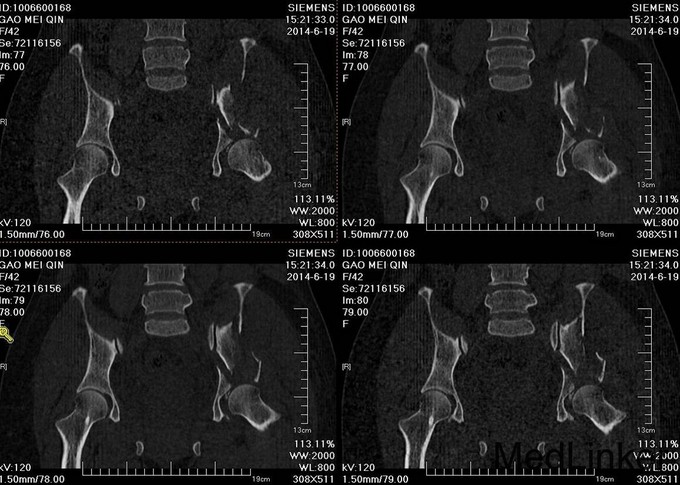

主诉:车祸外伤后左髋部疼痛伴活动受限4天 患者于2014年6月12日早6点左右被皮卡车撞伤,伤后患者出现一过性昏迷,被急诊送往当地医院,行DR及CT检查后,诊断为:左髋臼骨折,于当地医院骨科行骨牵引、抗炎补液等对症治疗后,现为求进一步治疗转入我科,患者病来无头晕头痛,无恶心呕吐,已排气排便.

患者左下肢股骨髁上骨牵引中,左髋部肿胀,臀部可见淤血瘀斑,骨盆分离挤压试验(+),左大腿肿胀,左下肢无明显短缩,纵向叩击痛(+),左下肢小腿外侧及足背麻木感,足背伸肌力正常,双足趾可活动,双侧足背动脉可触及搏动